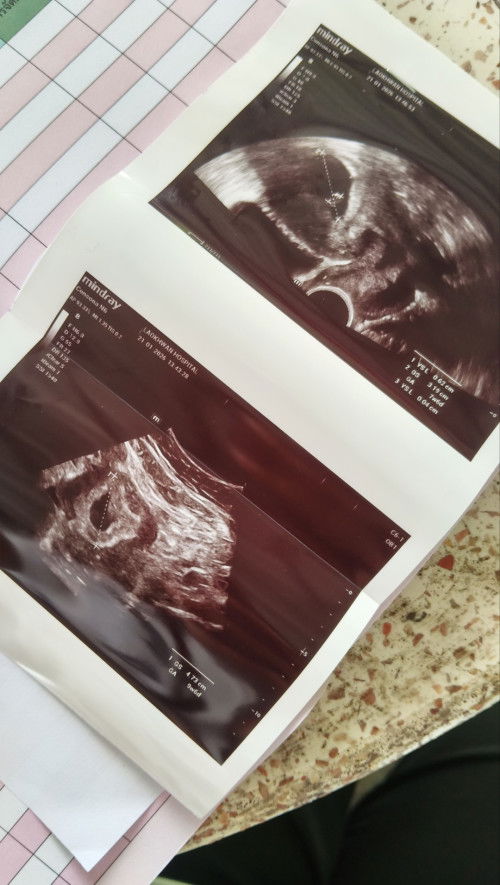

หมอได้ทำการ อัลตร้าซาวด์ ผ่านหน้าท้อง และ ช่องคลอด ในเครื่อง อัลตร้าซาวด์ บอกอายุครรภ์ว่า 7 สัปดาห์ 6 วัน แต่ถุงการตั้งครรภ์จริงๆ เล็กมากๆ เจอไข่แดง ตั้งครรภ์ในมดลูกปกติ หมอนัดอีก 2 สัปดาห์ เพื่อมาอัลตร้าซาวด์ แบบนี้ ผิดปกติไหมคะ กังวลมากๆเลยคะ 😢🥺 รอบประจำเดือนคือ วันที่ 2 ธันวาคม หมดวันที่ 9 ธันวาคม พ.ศ. 2568 ระยะเวลา 8 วัน รอบเดือน ยาว 35 - 36 วัน เป็นไปได้ไหมคะ ที่ไข่จะตกช้า

พอดีตั้งครรภ์ 6 week 4วันค่ะ เมื่อวานไปอัลตร้าซาวมาเจอถุงไข่แดง เจอถุงตั้งครรภ์แล้วแต่ยังไม่เจอเบบี๋ค่ะ ประมาณกี่สัปดาห์ถึงจะเจอน้องคะ คุณแม่ใจแป้วเลยค่ะ 🥹❤️#ช่วยบอกกันหน่อยนะคะ #ท้องแรก